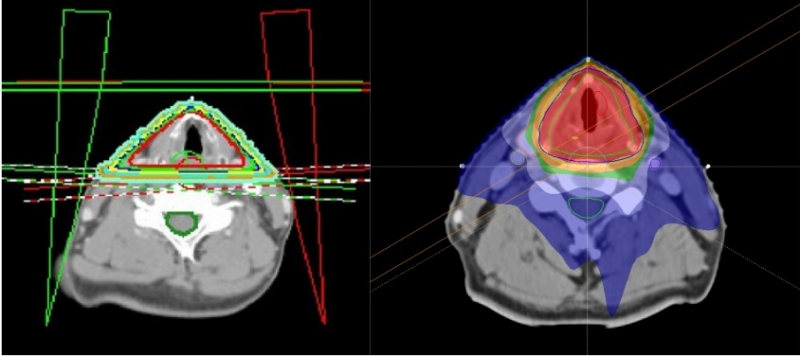

Background/aim: To compare survival outcomes and radiation-related toxicities between conventional radiotherapy (CvT) and volumetric-modulated arc therapy (VMAT) in patients with early glottic cancer.Patients and methods: We reviewed 81 patients with Tis-T2N0 glottic cancer who underwent definitive radiotherapy between 2010 and 2018. CvT (N=47) was delivered using two opposing lateral beams (70 Gy in 35 fractions), while VMAT (N=34) utilized two arcs (65.25 Gy in 29 fractions). Hypothyroidism was defined as an elevated thyroid-stimulating hormone level with or without a decrease in free T4 or T3 levels.

- 최근 early glottic cancer에도 VMAT을 적용하는 기관이 늘어나고 있습니다. Conventional technique에 비하여 carotid cartery, thyroid gland, esophagus에 조사되는 방사선량을 조절할 수 있다는 특징이 있습니다. 두 방사선치료 기법을 비교하여 VMAT으로 치료 받은 환자들이 생존율에는 차이가 없으면서 hypothyroidism 빈도는 낮았습니다. Carotid artery events와의 연관성은 장기간 관찰이 필요할 것으로 보입니다.

초기성문암의 통상적인 방식의 방사선치료(CvT)와 체적조절회전방사선치료(VMAT)의 치료 결과 및 부작용을 비교한 연구입니다. VMAT 치료법이 치료횟수를 줄이면서 갑상선기능저하와 목동맥 관련 부작용을 낮출 수 있었다는 점을 보여주면서 CvT에 비해 더 추천되는 방식임을 주장합니다. 다만, 통계적으로 유의하지 않았으나 (p=0.088) VMAT의 5년 국소제어율이 CvT에 비해 다소 떨어지는 것이 (95.4% vs 84.5%) 원인이 무엇이었을지 궁금한 부분입니다.